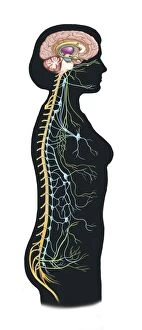

The central nervous system, the intricate network that governs our every thought and movement, is a marvel of complexity. From the delicate cerebellum tissue to the detailed light micrograph capturing its essence, we are reminded of its importance in maintaining balance and coordination. Anatomy comes alive as we explore the human brain from an inferior view. The intricacy of brain fibers is revealed through DTI MRI scans like C017/7099 and C017/7035, showcasing their vital role in transmitting information throughout this extraordinary organ. Artistic renderings bring us closer to understanding the medulla oblongata's significance within the brain. Its portrayal in various artworks allows us to appreciate how it controls essential functions such as breathing and heart rate. As we delve deeper into studying the central nervous system, models of the human brain provide invaluable insights into its structure and organization. Lateral views reveal countless regions responsible for cognition, emotion regulation, sensory perception, and motor control. Microscope slides offer glimpses into nerve cells' intricate architecture—a testament to their ability to transmit electrical signals at lightning speed. Meanwhile, glial stem cell cultures captured under a light microscope remind us of their crucial role in supporting neuronal function. Finally, artistic representations unveil the limbic system's enigmatic nature—an interconnected web responsible for emotions and memory formation. These captivating artworks allow us to visualize this complex network within our brains. Exploring these hints provides a glimpse into the awe-inspiring world of our central nervous system—the very foundation upon which our thoughts, actions, memories reside—reminding us just how remarkable our brains truly are.